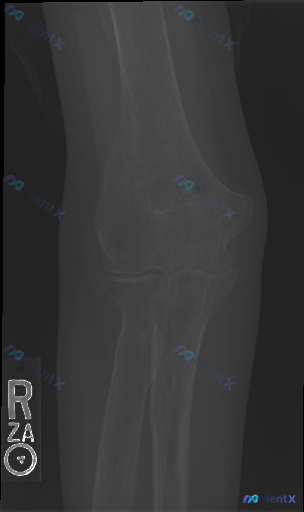

右肘正位片看起来“完全正常”,但临床仍有高风险漏诊点?

整理到一张右肘部正位的影像资料,先不说是在什么临床背景下拍的。

单纯从这张正位片来看:

- 肱骨远端、尺桡骨近端骨皮质连续性看起来还行,关节对合也没明显问题

- 没看到明确的骨折线、脱位,也没明显的骨质破坏、骨赘或者软组织肿胀

但如果告诉你这张片可能是外伤后拍的,而且患者还有肘部疼痛/压痛,会不会觉得这个“正常”其实藏着风险?

📋答案:1. 首要方向:需高度警惕**隐匿性骨折(如桡骨头边缘/冠突微小撕脱骨折)**;其次考虑单纯软组织/韧带损伤。2. 首选下一步:加拍右肘关节侧位片;若侧位仍不明确或临床高度怀疑,建议CT断层扫描(轴位+冠状位+矢状位)。